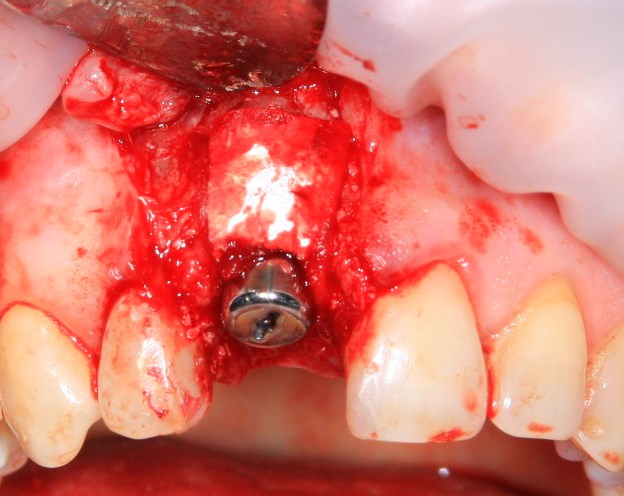

Немедленная имплантация — оптимальное решение в любой клинической ситуации